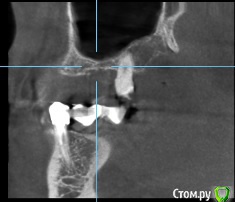

AAbdymomunov Опубликовано 24 июня, 2019 Поделиться Опубликовано 24 июня, 2019 Нужна помощь есть ли альтернатива вместо синуса? Пациент котегорически против синуса! 1 Ссылка на комментарий